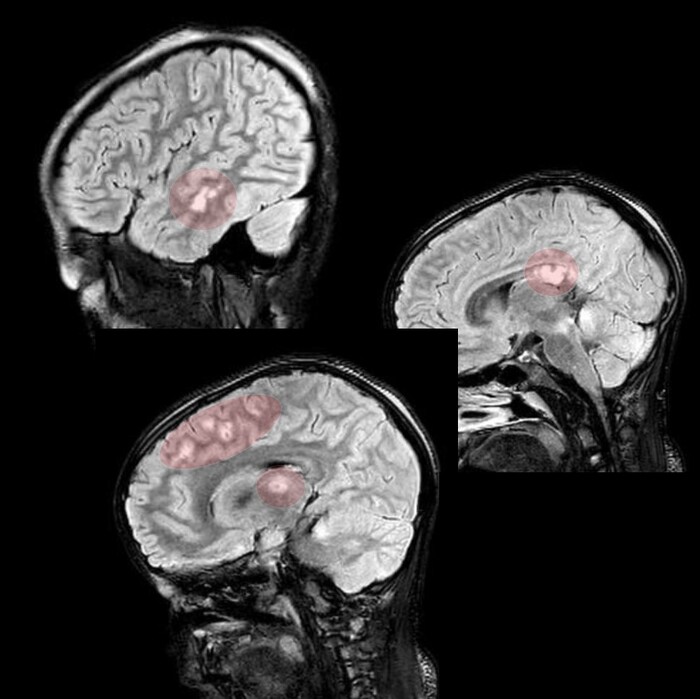

На 3й день после травмы из комы так и не вышла, посему сделали МРТ, на котором обнаружились участки повышенного сигнала на Т2-взвешенных изображениях на границе серого и белого вещества фронтально и темпорально справа, а также в область правого таламуса и в заднем отделе мозолистого тела т.н. сплениуме:

которые визуализировались и на FLAIR: